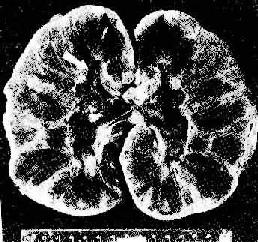

图4-6 肾移植急性排斥反应

肾肿胀,明显出血,肾盏及肾盂中充满血块